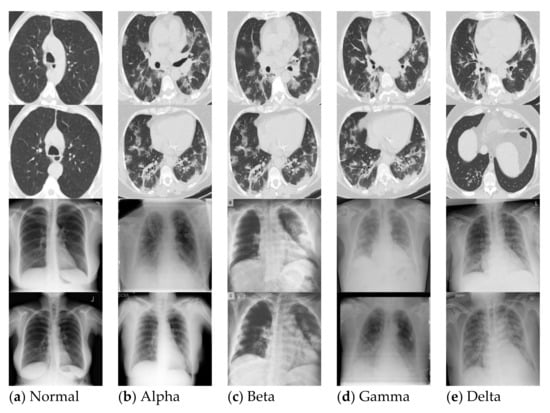

4. Experimental Results